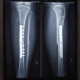

Selamat sore dokter, terkhusus dokter Spesialis Orthopedi

Mohon advisnya dokter

Jadi ada pasien mengeluhkan nyeri seperti tertusuk, tidak selalu, tapi sering, hilang timbul

Pasien post Orif ps H+113/6 bulan (tanggal 06 Agustus 2024)